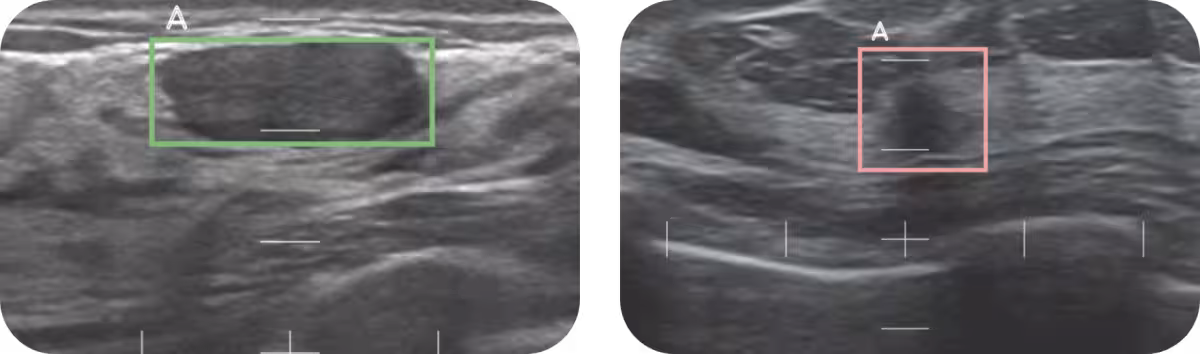

Smaopiは、既存の超音波検査装置と連携して機能します。画像診断支援ソフトウェア「スマートオピニオン METIS Eye」を用いることで、医師の読影をサポートし、診断精度を向上させます。このシステムは、従来の検査法と同様に痛みを伴わず、女性にとって快適な体験を提供します。AIは医師の診断を代替するのではなく、もう一つの目として活用され、結果的により高い精度を実現します。

「スマートオピニオン METIS Eye」は、高度に精密なAI診断支援機能を搭載しています。このプログラムは、医師が病変の可能性を評価する際に、AIを用いて精密検査が必要かどうかを判断します。これにより、検査の精度を94.4%という高水準に引き上げることが実現されます。